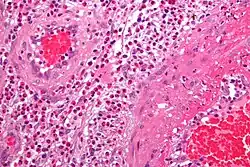

Feingeweblich zeigt sich eine starke Vermehrung eosinophiler Granulozyten im Gewebe (Gewebseosinophilie), mit Befall vor allem der kleinen Blutgefäße (mit Zerstörung, Blutgerinnselbildung und daraus resultierenden Infarkten). Daneben kann die Entzündung auch direkt auf verschiedene Organe übergreifen, z. B. auf das Herz mit der Folge einer eosinophilen Herzmuskelentzündung.